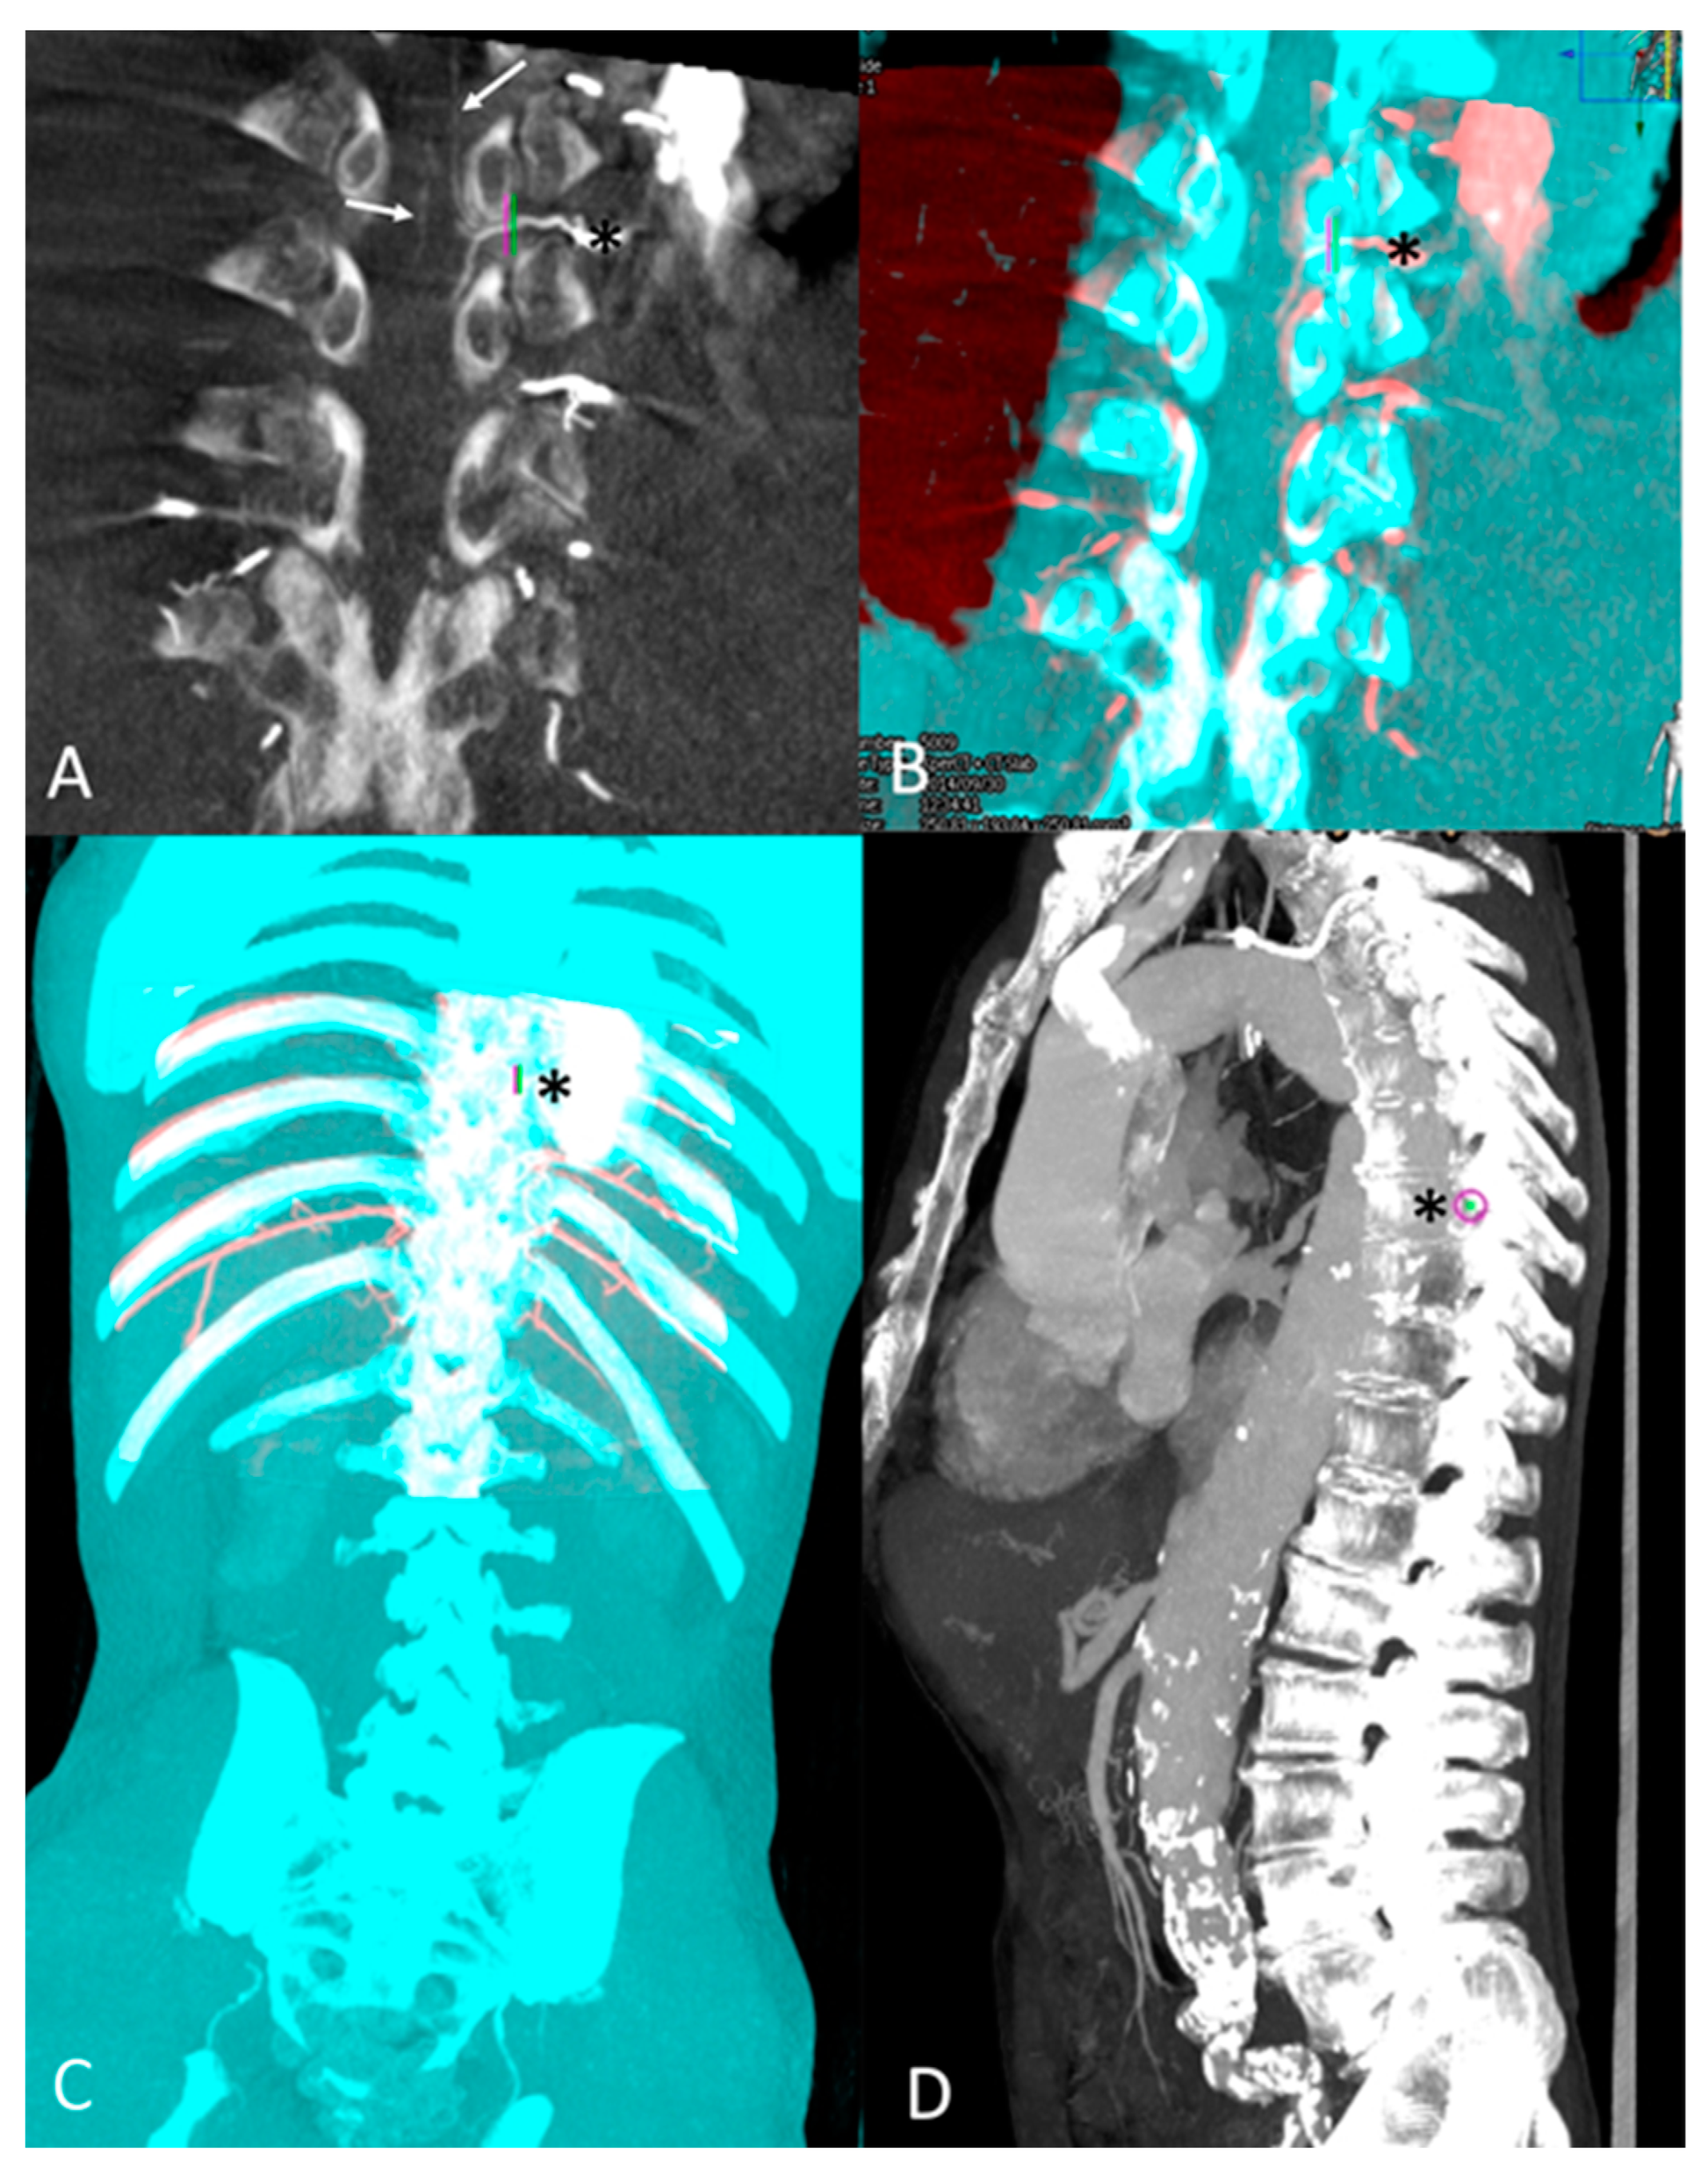

2.2. Procedure and CBCT Data Acquisition

2.3. Post-Processing and Image Analysis